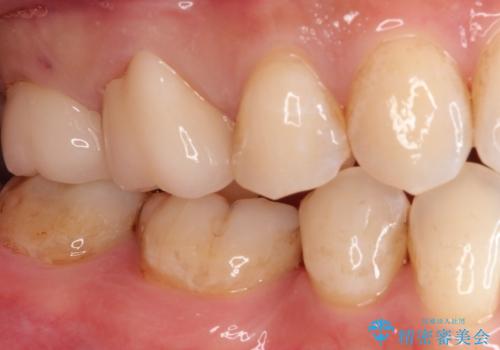

【オールセラミッククラウン】虫歯の治療

オールセラミッククラウンにて修復治療を行っております。

歯の破折強度を高めるためにクラウンによる修復を希望され、治療を行っております。